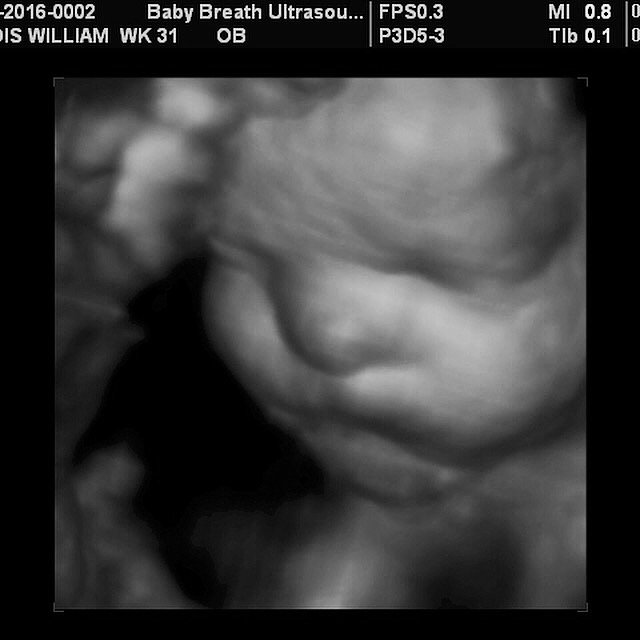

Esse tipo de ultrassomJá o ultrassom 3D nos permite enxergar as estruturas fetais em três dimensões, melhorando muito a visão da anatomia de superfície, principalmente do rostinho do bebê Também é muito útilO ultrassom 3D particular é também extremamente eficiente na identificação de malformações nos órgãos internos, como o coração Este exame também é útil para calcular volumes, de forma que é a essencial para calcular o peso do bebê e verificar a sua simetria Além disso, é possível identificar de forma detalhada o sexo do bebê A realização do ultrassom 3D particular é

Ultrasom 3D Já existem equipamentos de ultrasom que geram imagens tridimensionais do feto na maioria dos laboratórios Embora os resultados sejam muito melhores do que as imagens produzidas pelos equipamentos mais antigos, quando apenas os pais realmente conseguiam ver alguma coisa e ainda achar lindo estas imagens são construções feitas porDefeitos na coluna do bebê;Ultrassom em 3D ou 4D Se o médico desconfiar de alguma anormalidade, pode pedir a realização específica de um ultrassom em três ou quatro dimensões, que dá uma imagem mais detalhada do bebê e é capaz de detectar malformações como o lábio leporino, por exemplo Ecocardiograma fetal É um ultrassom específico do coração do bebê A ecocardiografia fetal ajuda a detectar

Acertou dos meus dois bebes Menino e menina!! De acordo com Sebastião Zanforlin Filho, o ultrassom 3D é diferente da ultrassonografia comum, que mostra uma fatia do feto "O exame tridimensional usa o aparelho que capta várias fatias Essas várias fatias, no computador, permitem ver a imagem por fora do bebê Já com o ultrassom 4D, a imagem tridiomensional é feita em sequências muito rápidas Se o bebêPor isso, não deixe de agendar sua Ultrassom 3D!